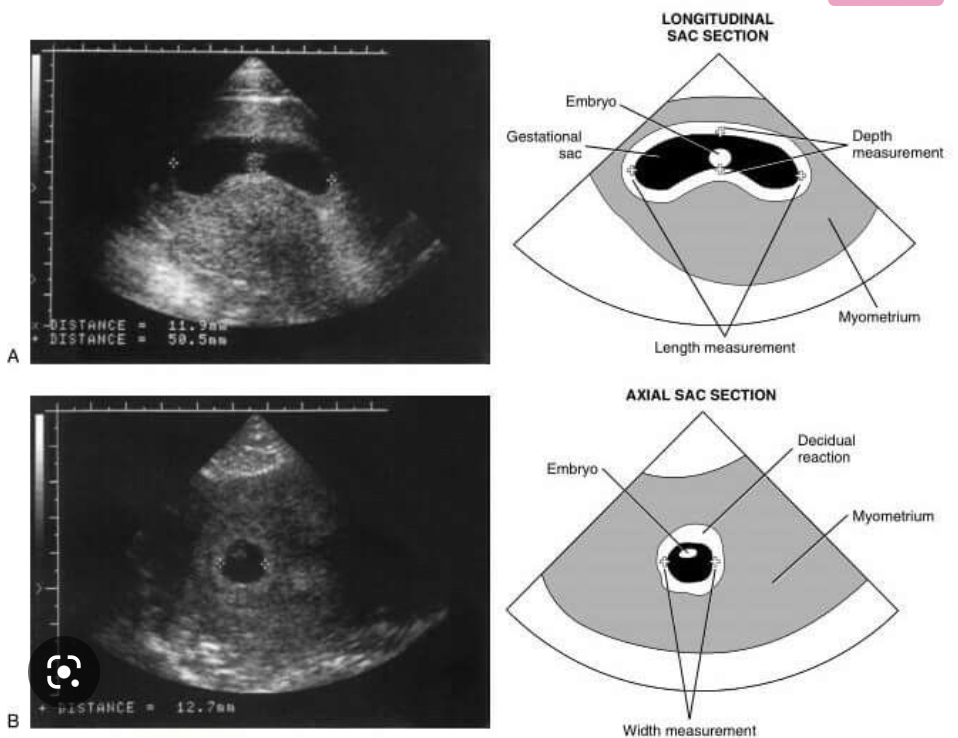

What 3 features are looked for on transvaginal US to determine the viability of a pregnancy?

A

• mean gestational sac diameter

• foetal pole + crown-rump length

• fetal heartbeat

mean gestational sac diameter

these appear sequentially so as each feature develops, the previous becomes less relevant in determining viability of a pregnancy

How is an anembryonic pregnancy diagnosed on transvaginal USS?

• a fetal pole is expected once mean gestational sac diameter is 25mm or more

• if the MGSD is >25mm and there is no fetal pole, scan is repeated after 1 week

• if the fetal pole is still not present, this is an anembryonic pregnancy